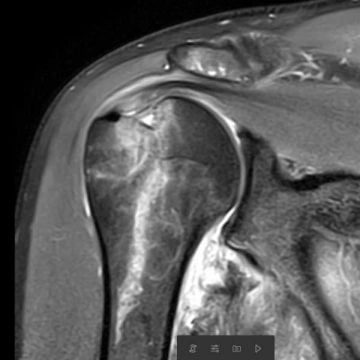

Magnetkameraundersökning (MR): Patienter över 50 år bör efter en axelluxation utredas vidare med en ultraljudsundersökning eller magnetkameraundersökning. Detta för att utesluta avslitna muskelsenor (rotatorcuffruptur).